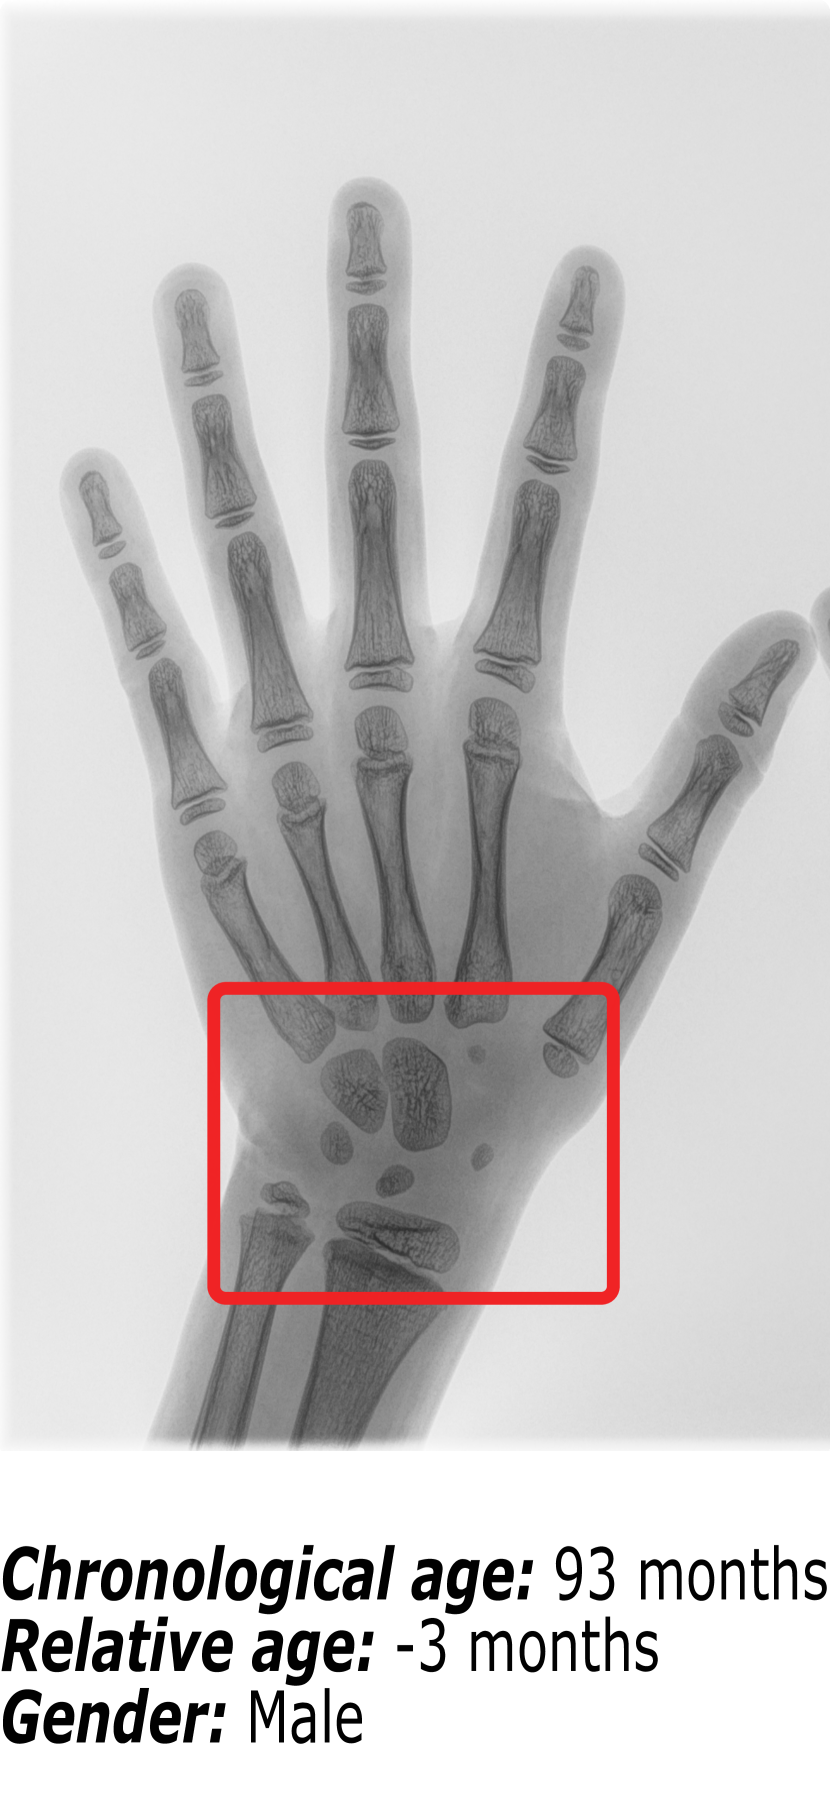

Figure 1 shows an example of the influence that identity markers have on bone age. The three hand radiographs present in Figure 1 belong to children with virtually the same chronological age. However, it is visible that the ossification patterns present in each of the hand radiographs vary significantly. First, gender is an important identity marker to take into account. Comparing Figure 1(b) (a female patient) and Figure 1(c) (a male patient), it is possible to observe that the bone structures in the region surrounded by the red box are more developed for the female than for the male. This finding is supported by the fact that skeletal development is faster in females than in males.

Nonetheless, when comparing two hand radiographs of patients of the same gender with the same chronological age, as it happens between Figure 1(a) and Figure 1(b), the expected result would be that the bone patterns did not vary much. Because most patients have a regular growth pattern, physicians use the chronological age as a starting point and compute the difference in skeletal development. This relative bone age between the patient’s chronological age and the patient’s bone age is the information that the radiologists use to diagnose growth disorders. However, Figure 1(b) belongs to a patient with regular growth, having a relative bone age of +1 month, while Figure 1(a) belongs to a patient with accelerated growth, hence the relative bone age of -38 months.